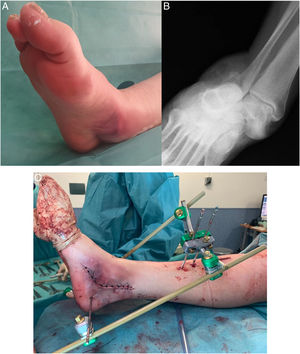

Median peritalar dislocation reduction was performed at 4h (3–5h of IQR) from the initial trauma, under general (7) or spinal (3) anaesthesia when carried out in the operating theatre (76.93%) or under intra-articular anaesthesia if reduction was achieved in the emergency department (23.07%). Surgery was required in six cases (46.15%) for different reasons (Table 2). On the one hand, four open dislocations required lavage, debridement, joint dislocation reduction, primary wound closure, and internal or external fixation. Conversely, of the two closed dislocations with unsuccessful attempts at closed reduction in the emergency department, one required, open reduction (Fig. 2) and, the other, closed reduction; in both cases in association with an external fixation (EF) device.

43-Year-old man with pain and deformity in his right foot after a traffic accident. A medial skin fold-groove suggestive of incarceration of tendon structures is seen in the context of a lateral subtalar dislocation (A). The anteroposterior radiograph shows a loss of subtalar congruity (B). An open reduction through a medial approach was required due to the incarceration of the posterior tibial tendon around the neck of the talus. After the reduction, an external fixator was implanted to control the stability and evolution of the soft tissues (C).

Of these six patients who needed some form of surgical fixation, the majority option in 5/6 cases was a delta-mounted external fixator. Internal fixation (IF) or percutaneous fixation was used in 2/6 cases: one patient needed K-wires in the astragalo-scaphoid joint and a transindesmal screw, in addition to EF; in the other patient, internal fixation was performed exclusively with a Steinmann pin in the subtalar joint and three k-wires (two in the talonavicular joint and one in the calcaneocuboid joint). As for the remaining seven cases (53.84%), closed reduction was undertaken in the ED or operating theatre with immobilisation with Walker or suropedic splinting (Table 2).